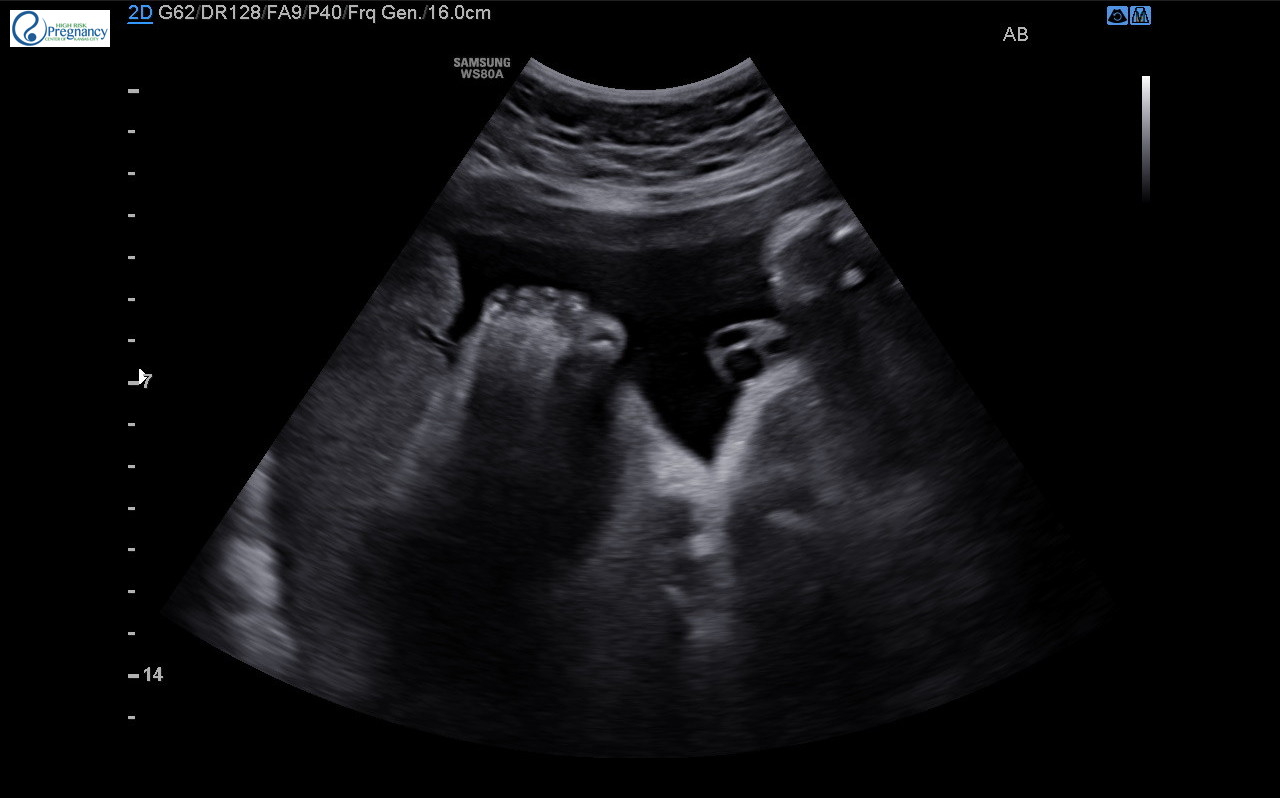

Had my weekly scan today, baby boy passed super quickly! Next week they'll check growth again during my scan and see how baby is weighing/measuring. Doctor inscreased my insulin another 4 units, I was hoping he'd only do 2 units otherwise things look good! And the tech got a super cute picture of baby toes!!!

Had my weekly scan today, baby boy passed super quickly! Next week they'll check growth again during my scan and see how baby is weighing/measuring. Doctor inscreased my insulin another 4 units, I was hoping he'd only do 2 units